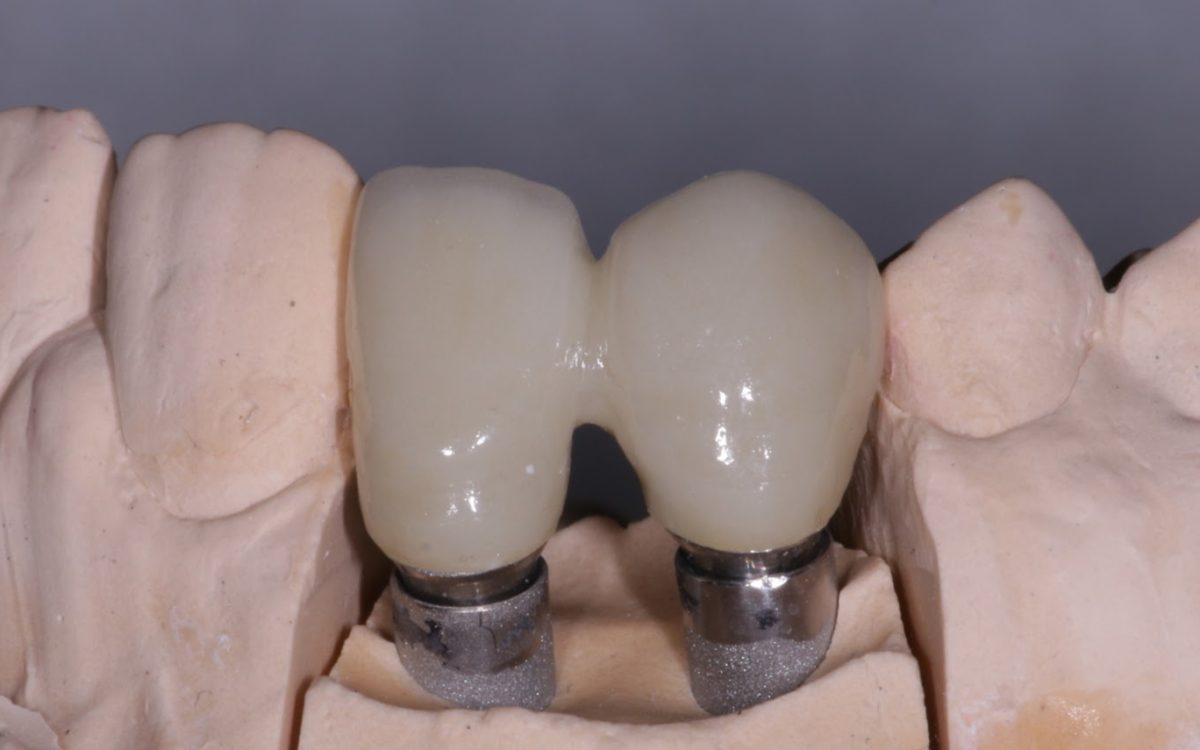

Az implantátum egy titániumból készült foggyökér formájú csavar, amit a foghiány helyére ültetünk be az állcsontban. Becsontosodása után kerül rá egy implantátum felépitmény és arra a fogpótlás, vagyis a korona. Jelenleg az egyik legmodernebb fogpótlási megoldás.

- Egy lenyomati fej segítségével lenyomatot veszünk.

- 2-3 próba után az implantátum fejre kerül a végleges, fogtechnikai labor által készített pótlás (korona, híd), ami általában további 1,5-2 hetet vesz igénybe.